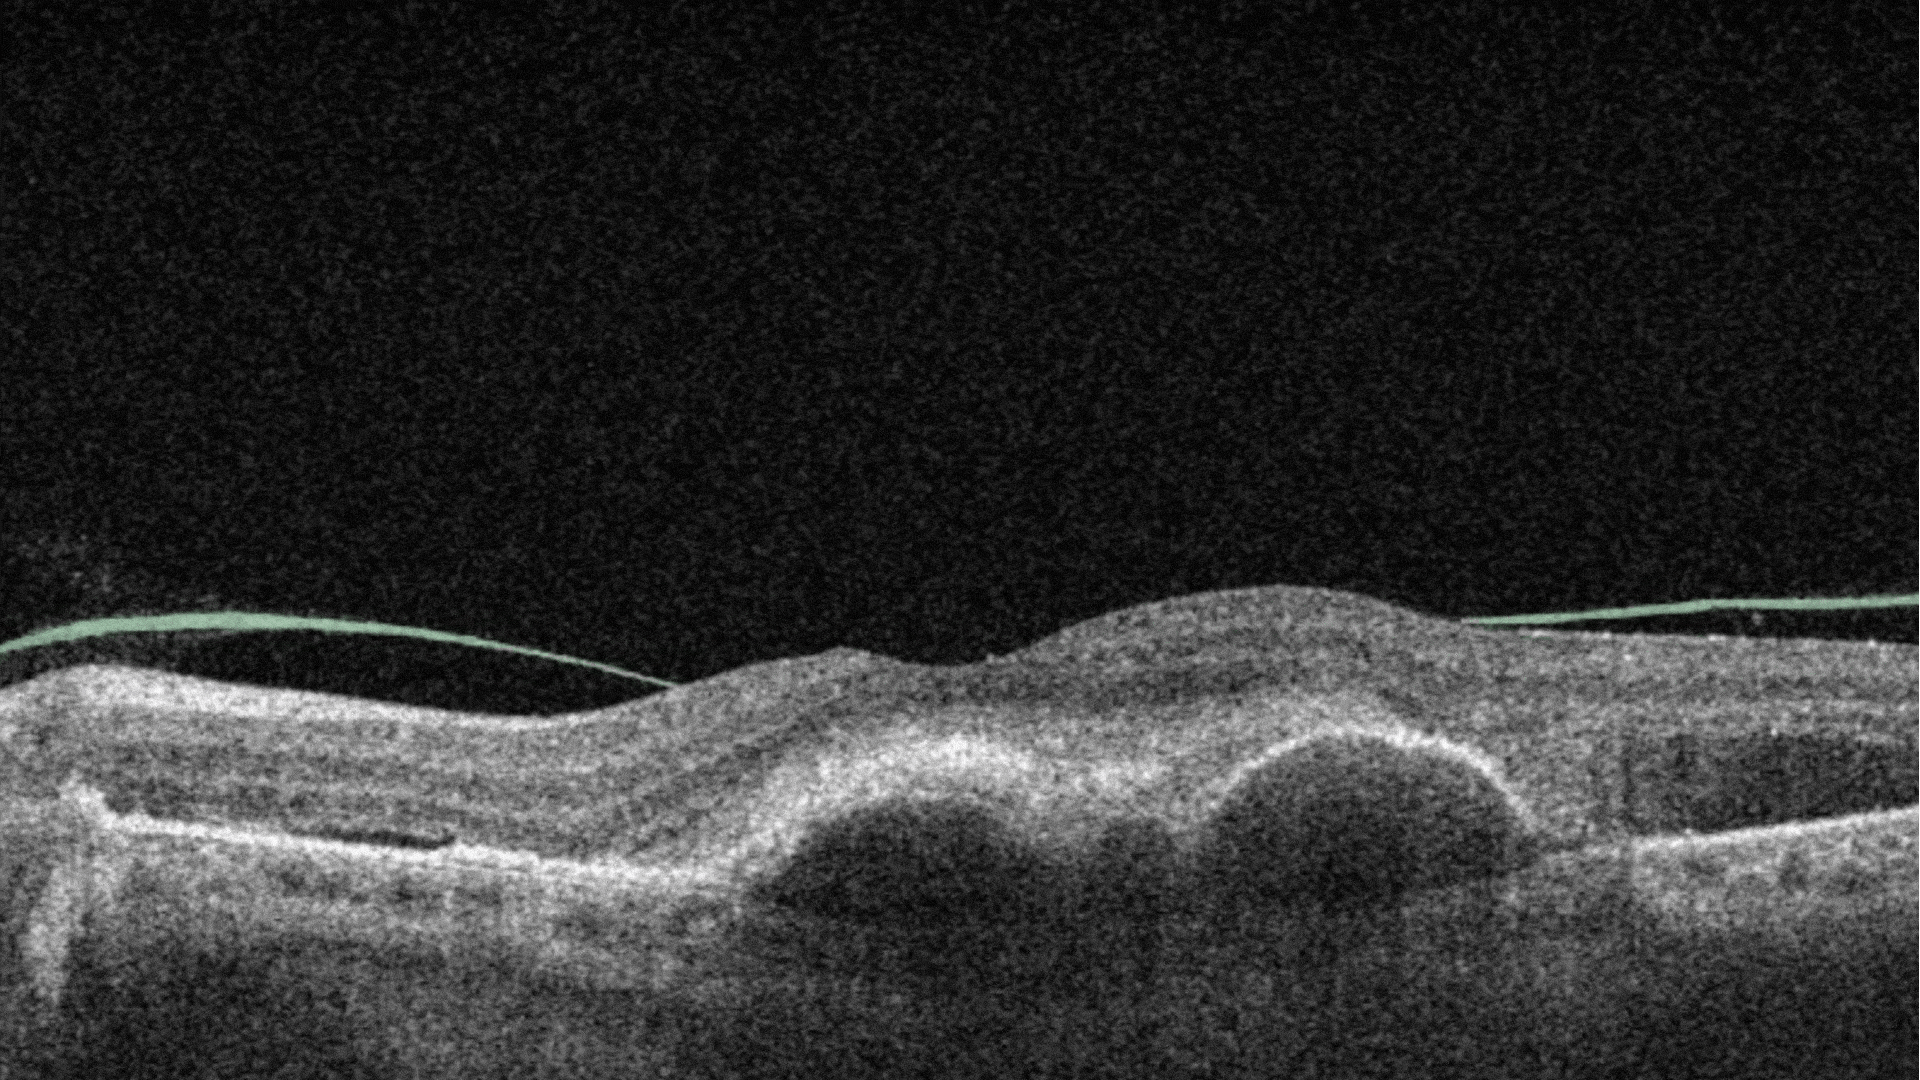

AI automates the selection of pathological OCT scans and the detection of 70+ pathologies and biomarkers.

More detailed screening means more early cases detected and more effective treatment as a result.